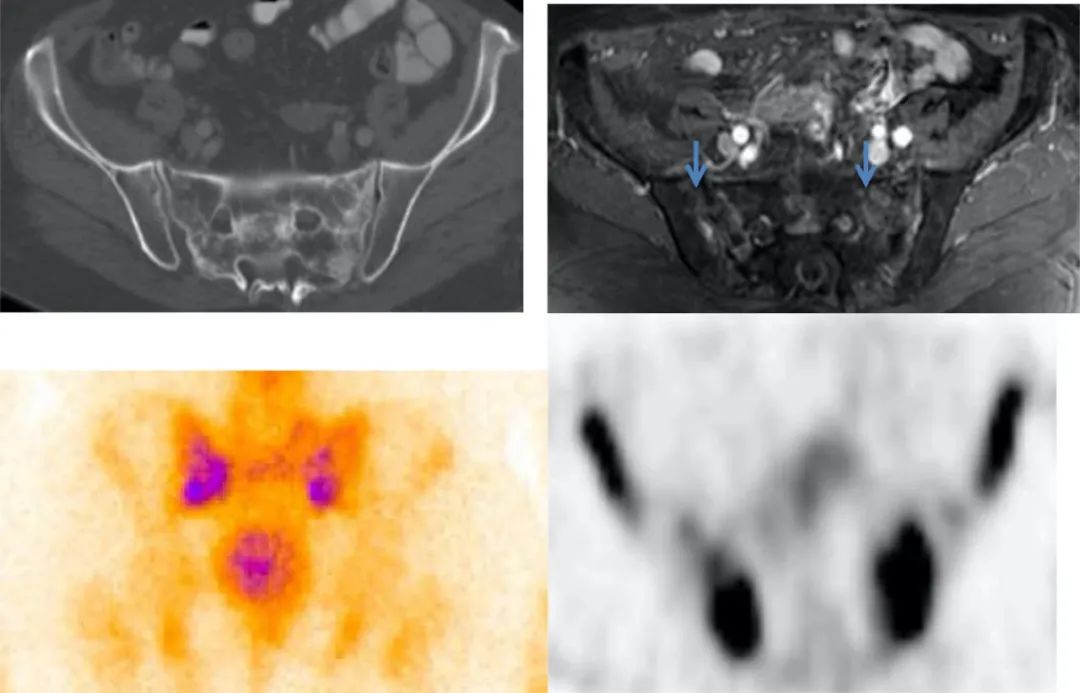

骶骨机能不全骨折的典型 18F-FDG PET/CT 表现为平行于骶髂关节的骨折线伴 FDG 摄取轻中度增高,PET/CT 显示病变的 FDG 摄取特征及形态学改变与转移瘤的鉴别诊断有重要价值。

女,55 岁,宫颈癌放化疗后 5 年发生骶骨机能不全骨折。PET/CT 骶骨横断面(A)、冠状面(B)显示双侧骶骨翼平行于骶髂关节骨折线,放射性摄取弥漫性轻度增高,沿骨折线处为著(箭);矢状面(C)显示骶骨体横行硬化骨折线,轻度 FDG 摄取(箭)